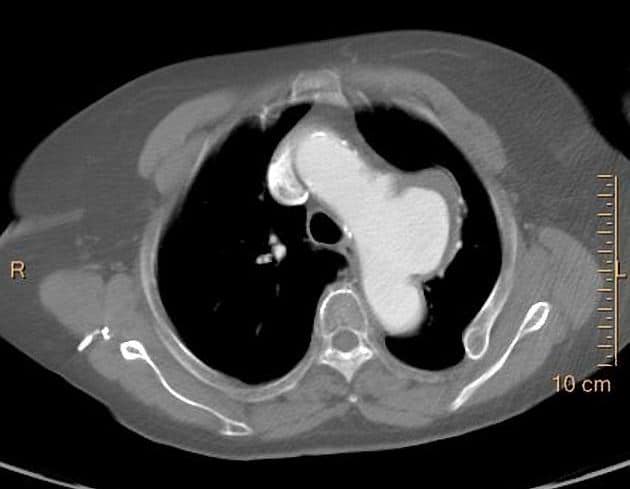

Phình ĐM chủ ngực

» Thông tin: Nam giới – 65 tuổi.

» Lâm sàng: Đau ngực.